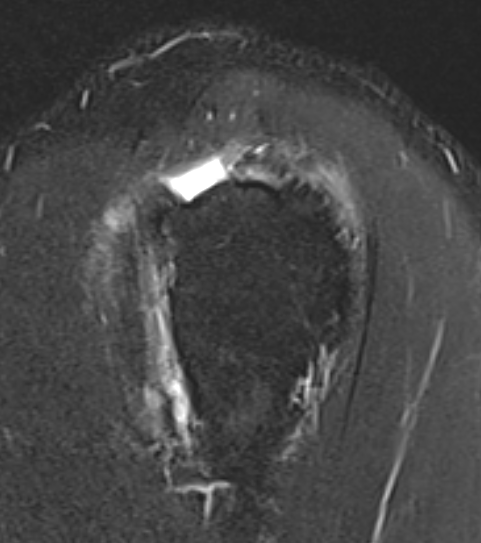

Goutallier classification

Amount of fatty degeneration in rotator cuff muscle belly on a T1 sagittal MRI

- systematic review of Goutallier grade and retear rates

- retear rates after surgical repair increase as the Goutallier stage increases

Equal fat and muscle MRI demonstrates grade 3 supraspinatus and infraspinatus |

More fat than muscle MRI demonstrates grade 4 infraspinatus |